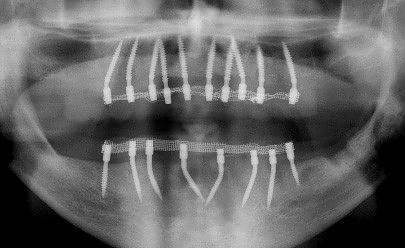

Implantát má v podstatě neomezenou životnost. Nutné jsou pouze kontroly u stomatologa a to 2 x za rok. Při dodržení dobré hygieny a pravidelných kontrol jsou implantáty velmi spolehlivé a úspěšnost této terapie se uvádí okolo 98 %.